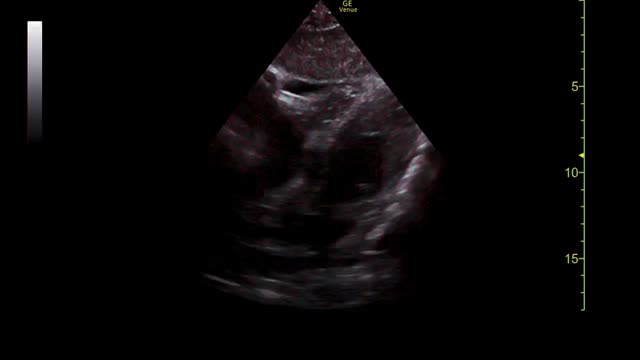

En ese momento, se realizó una ecocardioscopia que mostró buena función biventricular, ausencia de valvulopatías, de crecimiento de cavidades y de hipertrofia ventricular. Como hallazgo patológico destacó la presencia de un derrame pericárdico (fig. 1 y vídeo 1) que no llegaba a producir compromiso hemodinámico.

Con estos hallazgos, se llegó al diagnóstico de pericarditis aguda, cumpliendo 2 de los 4 criterios3: dolor típico y derrame pericárdico. En ese momento se inició tratamiento con 500mg de ácido acetilsalicílico con 2comprimidos en desayuno, comida y cena, asociando gastroprotección, y 0,5mg de colchicina (un comprimido al día durante 2semanas). Además, se suspendieron sus tratamientos previos (budesonida y lorazepam). Al alta, se derivó a la paciente a consultas externas de medicina interna para completar estudio.